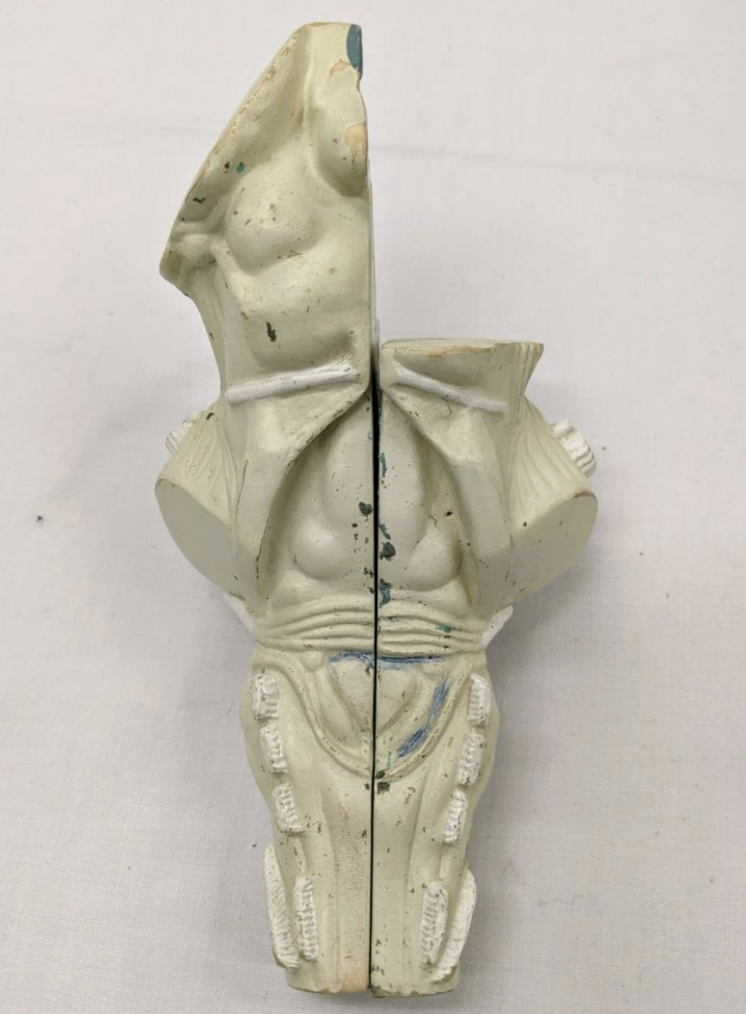

Cerebellum

Anterior lobe of cerebellum

Horizontal fissure

Posterior lobe of cerebellum

Cerebellar tonsils

Posterolateral fissure

Superior medullary velum

Arbor vitae

Folia